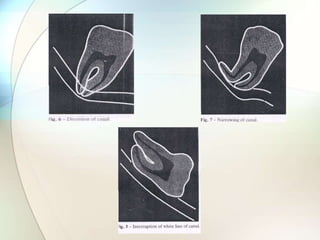

RELATIONSHIP OF THIRD MOLAR WITH

THE INFERIOR ALVEOLAR NERVE

Related but not involving the canal

Related to changes in the canal

Rood & Shebab criteria

(Rood JP ,Shihab BA - British J OMFS 1998:28:20)